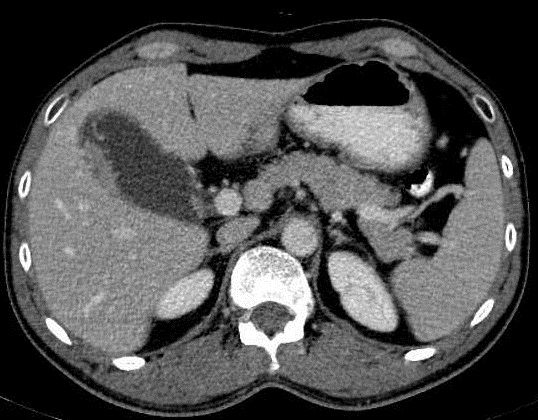

Aspect

radiologique TDM d'une adenocarcinoma au fond

de la vesicule biliaire : Image de prostruction

intramural a bord tres irregulie . Adenopathie

perihilaire peut en voyait . ( Image TDM + contrast

phase veineuse , en coupe axiale ) . |